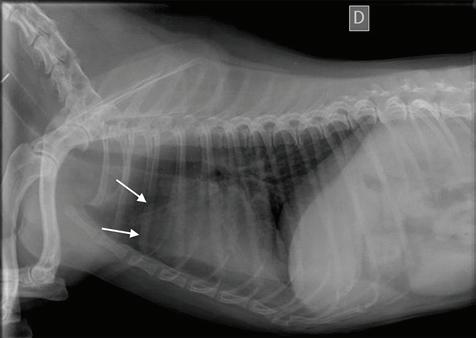

Se realizaron radiografías torácicas y en la proyección lateral derecha se observó, craneal a la silueta cardiaca, una opacidad tejido blando mal definida que producía efecto silueta positivo con esta. La tráquea se visualizó desplazada dorsalmente y el atrio izquierdo aumentado de tamaño. El parénquima pulmonar mostraba un aumento de opacidad en su área caudodorsal, compatible con un patrón pulmonar intersticial no estructurado difuso, el cual se consideró normal debido a que la radiografía fue tomada en fase espiratoria inicial

163

y a la condición corporal del paciente. En la proyección ventrodorsal, el mediastino craneal se observó en el límite superior de tamaño, presentándose un tamaño dos veces superior a la anchura de la vértebra torácica (Fig. 1). Este cambio es compatible con una imagen artefactual secundaria a la leve rotación que presenta la radiografía y a la condición corporal del paciente. El diagnóstico radiológico más probable fue una masa mediastínica craneoventral y cardiomegalia izquierda. En la ecocardiografía transtorácica se confirmó el diagnóstico de enfermedad degenerativa de la válvula

Figura 1. Radiografías torácicas en proyección lateral derecha (A) y ventrodorsal (B) donde se visualiza el área de opacidad de tejido blando craneal a la silueta cardíaca (flechas blancas). En la proyección ventrodorsal se visualiza el mediastino craneal que se presenta en el límite superior de grosor (flechas rojas).